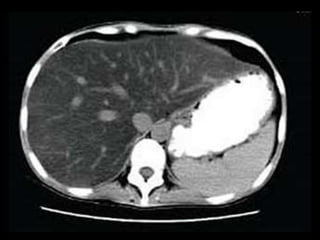

HIGADO NORMAL